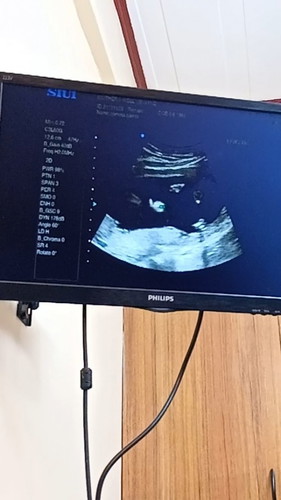

My Baby waving in my Tummy

Share ko lang po 5months pregnant transverse po bay ko nag pa ultrasound ako nakaaran araw then nakita ko sa monitor na he/she waving dpa sure ung gender